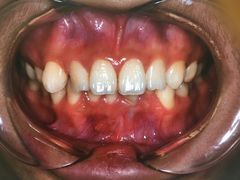

• 固瑞齿科(国贸门诊店)

• -固瑞齿科(国贸门诊店)

点小评4457552211 | 18-12-31

报错